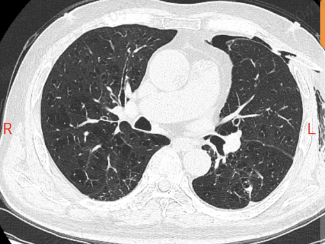

他这肺就像个漏气的气球,气胸反反复复,隔几周就得住院抽气、插管子,CT 片上的肺大疱密密麻麻,医生说这是难治性气胸,传统手术风险不小。

手术前,团队用 3D 成像把病灶看得清清楚楚。